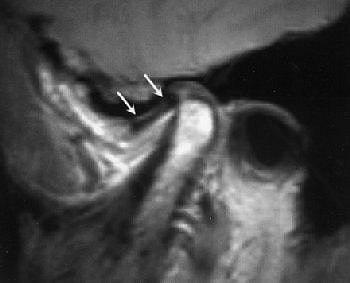

Fifty-year-old woman with clicking and pain in both TMJs, 8-mm mandibular advancement, and MIO that decreased from 42 mm to 40 mm postoperative. Above, bilateral, right anterior disk displacement on MRI preoperative, which did not change on postoperative MRI, below. Images courtesy of Dr. Jessica Lee.